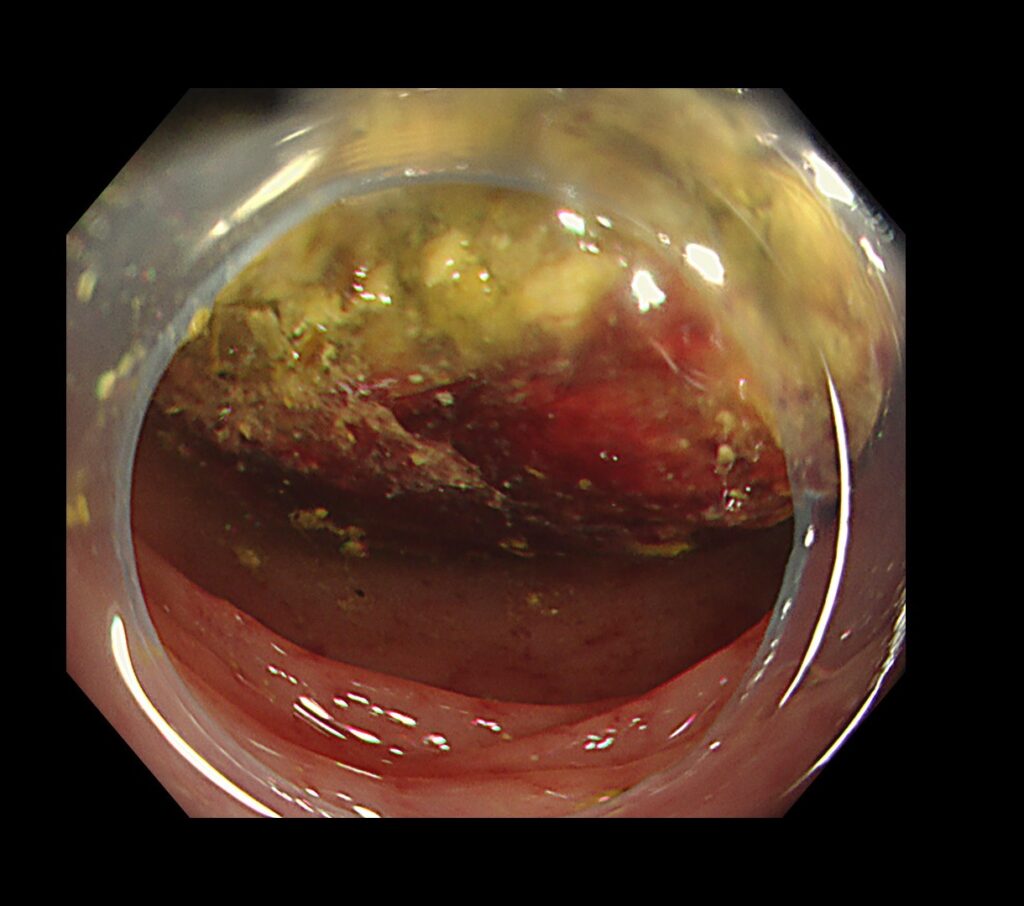

原因精査のため、無送気(水浸法による内視鏡挿入:水をいれて視野を保つ方法)で大腸カメラを挿入しました。

※空気を入れた挿入すると、病態の増悪を誘発するため。

糞石による閉塞性大腸炎をきたしており、粘膜からの出血と腸に嵌頓する糞石を認めました。